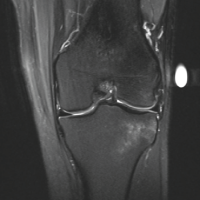

We present the case of a 35-year-old female who presented 3 weeks post-traumatic injury to her elbow. She had a fall on the flexed elbow with force directed through the olecranon tip proximally. She was initially managed with a splint in 90° elbow flexion and forearm supination. She was advised conservative management for the fracture, including immobilization for 8 weeks followed by gradual physical therapy; however, she presented to us due to constant pain and restricted elbow range. On examination, she exhibited swelling and tenderness over the medial elbow without wounds or distal neurovascular deficit. Plain radiographs of her elbow showed a half-moon-shaped fragment displaced anterosuperiorly with irregular ulnohumeral articulation in the lateral X-ray. No dislocation of the elbow joint or the radial head was noted. These findings were corroborated on subsequent computed tomography (CT) scans (Fig. 1 and 2).

Figure 1: Anteroposterior and lateral radiographs showing anterosuperiorly displaced trochlear fragments.

Figure 2: Computed tomography scan sections showing the displaced trochlear fragment marked in a circle on (a) axial, (b) coronal, and (c) sagittal cuts.